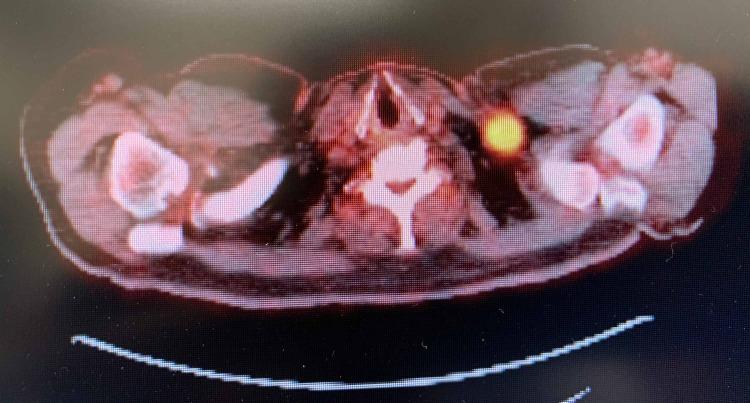

Pembrolizumab is an immune checkpoint inhibitor approved for use in many cancer types such as non-small cell lung cancer (NSCLC), metastatic melanoma, head and neck cancers, hepatocellular carcinoma, and renal cell carcinoma. There are many reported cases of patients on immunotherapy who have discontinued treatment due to the development of immune-related adverse effects (irAE). Recognition of the histopathologic patterns of dermatologic toxicities due to immunotherapy will become increasingly important for ensuring appropriate management and optimal patient care. Here, we present a case of a 72-year-old man with metastatic carcinoma of unknown primary origin treated with pembrolizumab who developed an immune-related cutaneous adverse event (ircAE) in the form of lichenoid dermatitis.

帕博利珠单抗是一种免疫检查点抑制剂,已被批准用于多种癌症类型,如非小细胞肺癌(NSCLC)、转移性黑色素瘤、头颈癌、肝细胞癌和肾细胞癌。有许多关于接受免疫治疗的患者因出现免疫相关不良反应(irAE)而停药的报道病例。认识免疫治疗引起的皮肤毒性的组织病理学模式对于确保适当的管理和最佳的患者护理将变得越来越重要。在此,我们报告一例72岁男性患者,其原发灶不明的转移性癌接受帕博利珠单抗治疗后出现了苔藓样皮炎形式的免疫相关皮肤不良事件(ircAE)。